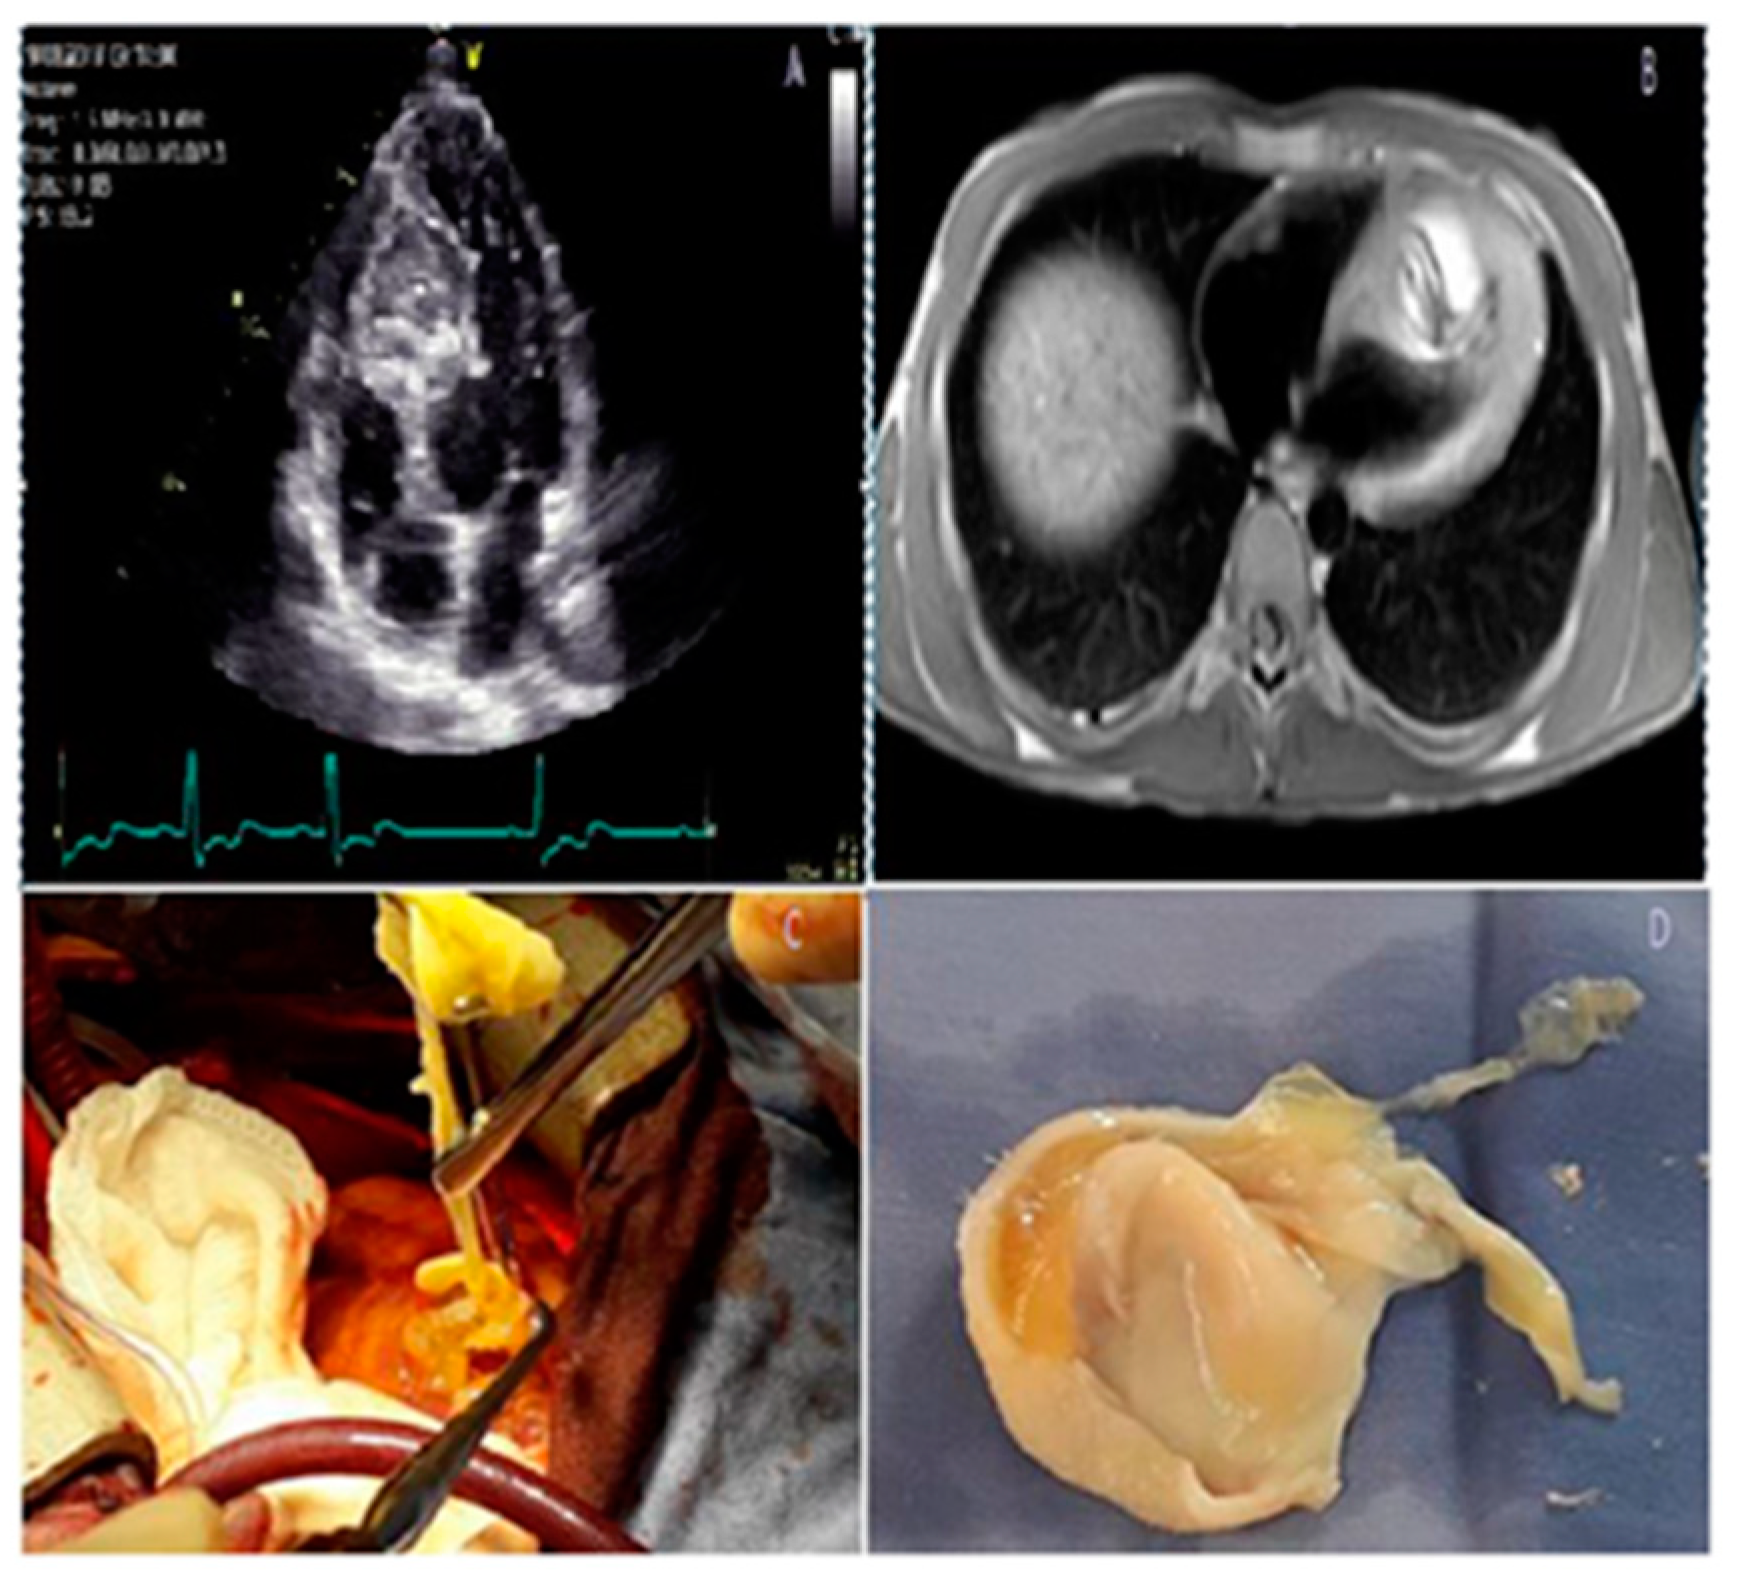

Figure 1.

Complex mechanisms leading to dynamic obstruction in a patient with HCM. Concentric hypertrophy involving mainly the basal septum (diastolic IVS thickness of 15 mm), and elongated mitral leaflets with systolic anterior motion (A); M-mode echocardiography shows the systolic contact of the mitral valve with the IVS (arrows) (B); anterior displacement of the hypertrophied papillary muscles (C,D); moderate eccentric (posteriorly oriented) mitral regurgitation secondary to SAM (E); and significant resting LVOT obstruction by CW Doppler (peak resting gradient of 102 mmHg) (F). Of note, there is severe LVOT obstruction without severe septal hypertrophy, explained by the significant abnormalities of the mitral valve apparatus. HCM hypertrophic cardiomyopathy, IVS interventricular septum, LVOT left ventricular outflow tract. Mandeş L, et al. Journal of Echocardiography 2020; 18: 137–148 [39].